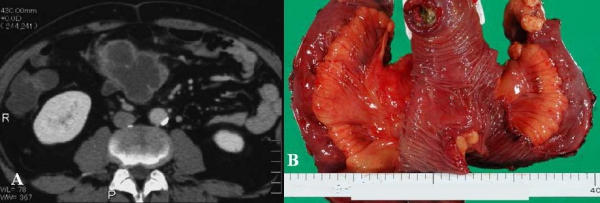

Hình 24: Túi thừa Meckel lộn ngược ở bệnh nhân nữ 61 tuổi. A, Hình siêu âm thấy “target sign” với vùng trung tâm là mỡ echo dày. B, đại thể: túi thừa Meckel lộn ngược, niêm mạc đỏ phù nề (mũi tên) (Angela D. Levy, Christine M. Hobbs (2004). Meckel Diverticulum: Radiologic Features with Pathologic Correlation. RadioGraphics 24:582)